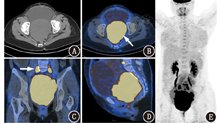

患者女,32岁,因"阴道不规则出血伴下腹痛1周"入院。患者1周前无明显诱因出现阴道出血伴间断性下腹痛,无发热、恶心、呕吐,无腹胀、腹泻等。有剖宫产史。体格检查:阴道内触及较大质硬包块,宫底脐下三横指,轮廓清楚,质中,余未见明显异常。实验室检查:鳞状细胞癌相关抗原0.8[0~1.5(括号内为正常参考值范围,下同)] μg/L;血常规:Hb 109(115~150) g/L;尿常规:RBC 322.4(0~17.6)×106/L,白细胞1 404.3(0~15.4)×106/L,上皮细胞62.9(0~8.7)×106/L,隐血3+(阴性),白细胞酯酶3+(阴性),尿蛋白1+(阴性);余指标未见明显异常。影像学检查:盆腔彩超示盆腔内大小约11.5 cm×11.6 cm低回声区,位于阴道中上段水平,与宫颈关系密切,内见少许血流信号。盆腔MRI示盆腔内占位,与子宫颈分解不清,考虑子宫颈癌;盆腔内多发肿大淋巴结,考虑淋巴结转移。18F-脱氧葡萄糖(fluorodeoxyglucose, FDG) PET/CT(上海联影医疗科技有限公司uMI510型)显像示:盆腔内骶前区巨大软组织肿块,与子宫颈及阴道中上段分界不清,糖代谢异常增高,最大标准摄取值(maximum standardized uptake value, SUVmax)为24.9(图1),延迟显像(注射后2 h)SUVmax为37.0,考虑恶性肿瘤性病变;盆腔内双侧髂血管旁多发肿大淋巴结,糖代谢异常增高,SUVmax为23.5(图1),延迟显像SUVmax为28.6,考虑淋巴结转移;全身其余部位未见异常高代谢灶。阴道镜检查:阴道内约9 cm×12 cm包块,质硬、色白、表面光滑,取少许占位性病变组织行活组织检查(简称活检),病理示:(子宫颈)光学显微镜下见红染无结构坏死物及炎性渗出物;(阴道)光学显微镜下见肿瘤细胞由上皮细胞构成,呈圆形、卵圆形,核深染,核仁少见,细胞质缺乏,核分裂象易见(图2),提示小圆细胞恶性肿瘤;免疫组织化学分析示突触素(synaptophysin, Syn;+)、嗜铬粒蛋白A(chromogranin A, CgA;+)、CD56(+)、波形蛋白(vimentin, Vim;+)、细胞增殖核抗原Ki-67(90%)、甲状腺转录因子-1(thyroid transcription factor-1, TTF-1;+)及细胞角蛋白18(cytokeratin 18, CK18;+)。诊断:阴道小细胞神经内分泌癌(small cell neuroendocrine carcinoma, SCNEC) ⅢC1期。患者阴道肿块较大,分期较晚,不适宜行手术,予"依托泊苷+顺铂"化疗。

阴道原发性SCNEC的影像学表现无明显特征性,CT多表现为阴道壁不均匀增厚,局部形成软组织肿块,边界不清,内部密度不均匀,增强后呈轻中度强化;MRI上病灶呈不均匀长T1、长T2信号,弥散加权成像(diffusion weighted imaging, DWI)呈高信号,增强后呈轻中度强化,常伴有盆腔及双侧腹股沟区多发肿大淋巴结;18F-FDG PET/CT显像表现为病灶18F-FDG摄取明显异常增高,转移灶亦呈明显异常高代谢[7]。该肿瘤侵袭性高,病变多呈浸润性生长,与周围组织分界不清,部分累及子宫颈或直肠,易发生周围淋巴结转移及远处转移。本例阴道肿块及盆腔肿大淋巴结18F-FDG摄取异常增高,提示恶性肿瘤性病变伴淋巴结转移;全身其余部位未见异常转移灶。

18F-FDG PET/CT显像虽然不能对阴道肿块进行明确诊断,但在病变良恶性的判断及显示淋巴结转移与远处转移上具有明显优势,对早期诊断及临床分期有重要价值,有助于治疗方案的选择。本例18F-FDG PET/CT显像盆腔内阴道中上段软组织肿块及周围肿大淋巴结糖代谢摄取异常增高,结合患者MRI及阴道镜检查可明确病灶为来源于阴道的恶性肿瘤,伴淋巴结转移。阴道肿块及盆腔淋巴结转移灶糖代谢均异常增高,SUVmax高达23.5~37.0,与Tamura等[7]报道的阴道SCNEC及其转移灶18F-FDG摄取增高相符。阴道SCNEC远处转移患者较少见,Yan等[5]曾报道了1例肺转移患者。本例暂未发现有远处转移。